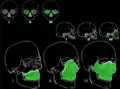

Kraniofaciální chirurgie – posuny lebečních a obličejových kostí při syndromových deformitách (např. m. Crouzon) -